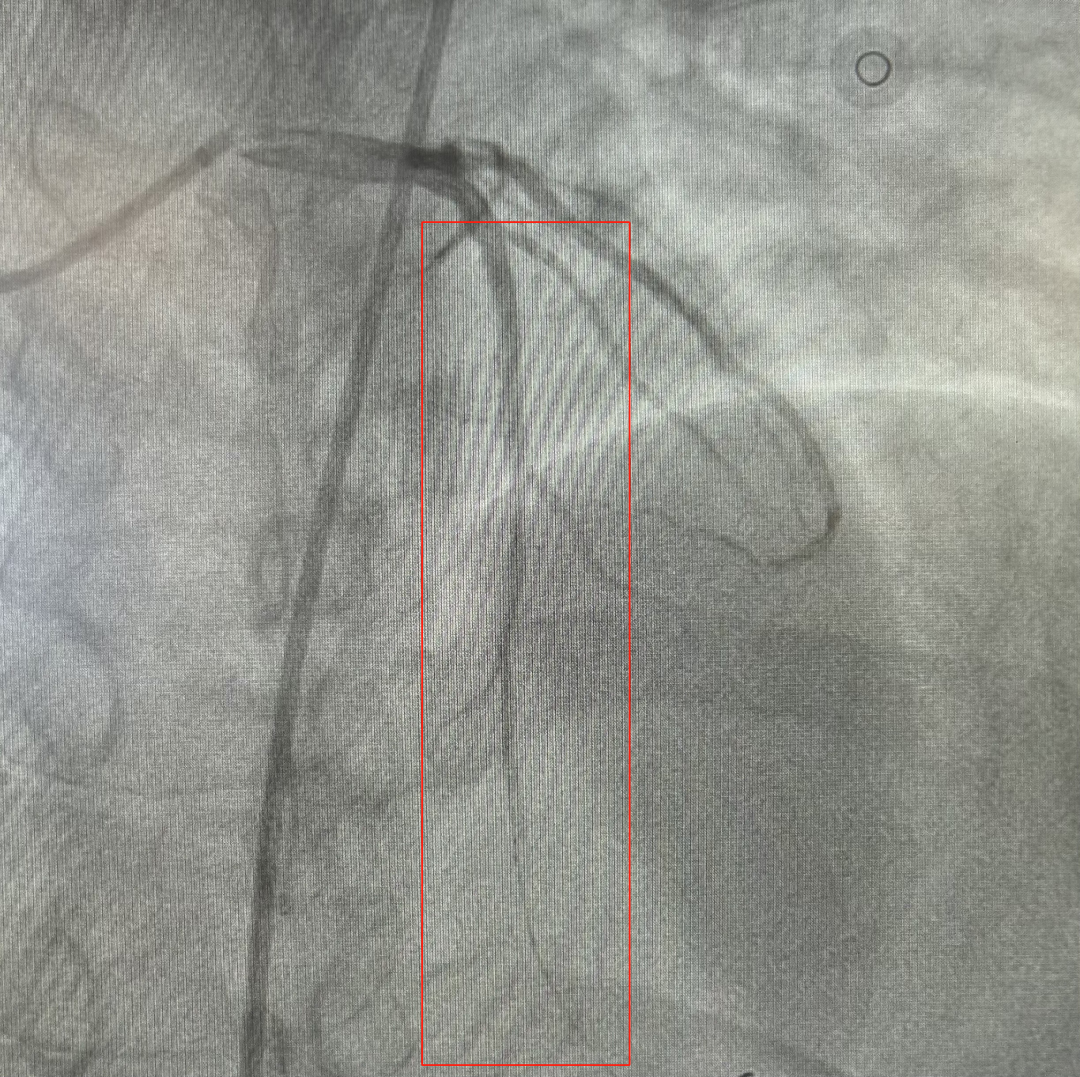

13时27分,顺利完成冠状动脉造影,造影结果显示前降支近段完全闭塞,并可见血栓影。

闭塞血管开通恢复正常血流

该院医生操控导丝迅速通过闭塞处,用抽吸导管抽吸出几块白色血栓,复查造影见前降支恢复了血流,但前降支近段仍有80%的狭窄。此外,在其狭窄处,医生还植入了一枚支架,成功恢复血管的通畅,实现了血运重建。手术在13时38分顺利完成,及时阻止了心梗进一步恶化,方先生的胸痛症状因此得到了明显缓解。